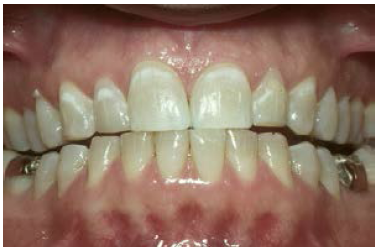

Angle Classifications: Class I malocclusion (Figure 1) has a normal molar relationship. Although the molars may be in ideal position, the other teeth may be crowded, rotated or have excess spacing.

Figure 1. Class I malocclusion.

Figure 1